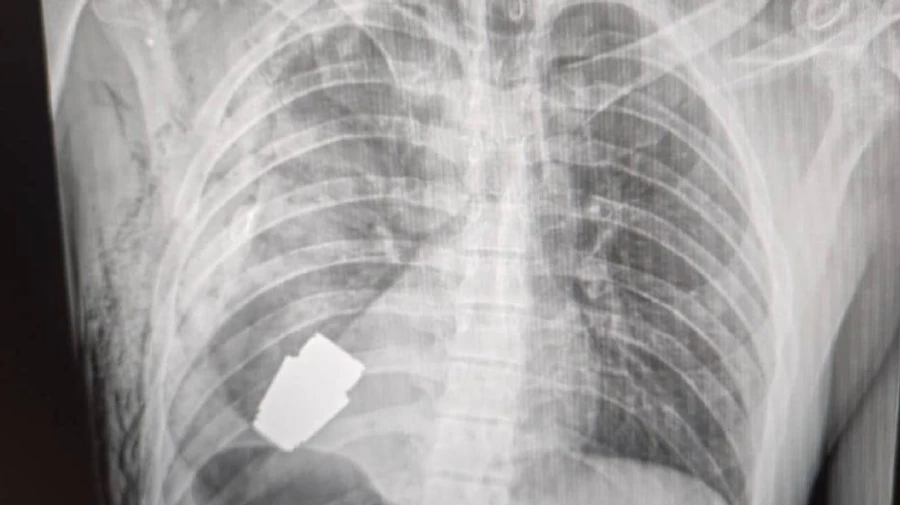

Ukrainian doctors have performed a unique surgery, retrieving an unexploded VOG-25 grenade out of a soldier’s body.

Quote: "Not every wound to the heart is fatal! Military doctors performed an operation to remove an unexploded VOG grenade from the body of a serviceman.

It was removed in the presence of two sappers who ensured the safety of medical personnel.

The operation was performed by Andrii Verba, one of the most experienced surgeons of the Armed Forces of Ukraine; [it did] not [involve] any electrocoagulation, as the grenade could have detonated at any moment."